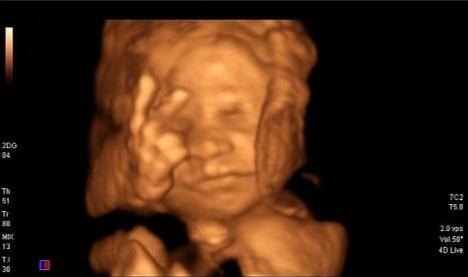

这种情况也很常见,我们可以从网上看到很多胎儿捂着脸的四维照片,很多孕妈妈诉苦说“宝宝总是捂着脸,一会儿捂鼻子、一会儿捂脑袋、一会儿捂嘴巴,做个四维真的很费劲。”

胎儿手的位置基本处于向上的状态,不是摸头,就是揉眼睛、捏鼻子、吸吮手指。这些都是他日常的一些活动,没有什么特别的。当胎儿出生以后,宝宝的手总是向上举着,呈现投降的姿势,就是因为在子宫里形成的习惯。

做四维彩超的时候,探头会有热效应,胎儿会感觉到这种热,有些不舒服。同时探头在肚皮上滑动时,对胎儿有触碰。这时的胎儿触觉敏感,他会下意识地提高警惕,捂住脸是一种最自然的表达方式。